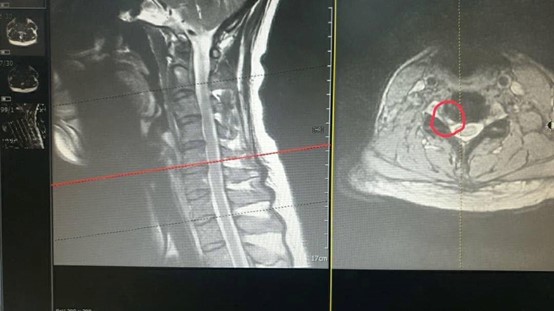

圖文:黃永昇院長/提供。

一位48歲林性女性患者,因從事醫護和文書作業,長期低頭工作,因出現右側上肢偏麻、尤其是第1-3指麻木感、頭暈及頭痛等症狀,MRI檢查顯示頸椎第3-7椎間盤突出,神經外科建議以微創手術治療,復健科建議可嘗試復健拉脖子,患者經歷一年復健後雖日常功能恢復,仍持續出現間歇性頭痛與肩頸麻痛,右手第1-3指麻,遇外在壓力或姿勢不良時症狀加劇,甚至誘發偏頭痛。因緣際會至詠昇中醫院所接受中醫治療,經黃永昇院長評估可能是富貴包,並壓迫下頸椎神經根,產生手麻、頭痛等現象,因此採以針刀鬆解、針灸疏通經絡及傷科牽引手法為主軸之綜合治療,治療期間輔以復健牽引與肌筋膜放鬆訓練,每週治療1至2次,持續約1個月,治療後患者主訴頭痛與肩頸麻木顯著改善,頸項活動度提升,夜間疼痛減輕,偏頭痛發作頻率下降。目前持續進行中醫調理追蹤中。